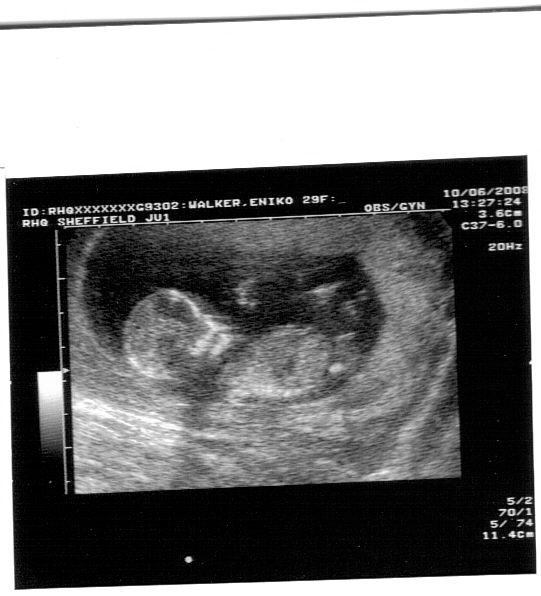

Babuci 13 hetes 1 napos